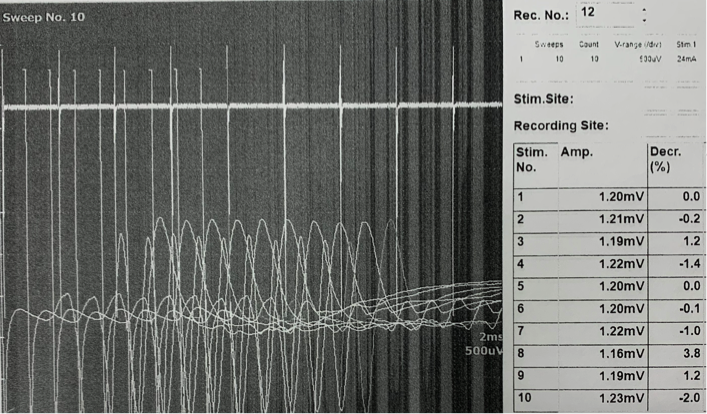

脛骨神経に2秒間隔で10回刺激を加えて、対応する筋肉の活動電位の変化をみる検査を実施しました。

重症筋無力症では4-5発目の刺激で活動電位の10%以上の低下を生じることが知られています。写真は実際の検査時の記録です。

Decr.という項目が1発目と比較した減少率を示しています。この症例では4発目に11.2%の減少が認められています。

2枚目の写真ではテンシロンを投薬した後の同様の検査となります。

投薬後の減少率は改善しており、効果が確認されました。薬の効果が切れた頃に再度実施すると減少率は10%以上を示していました。